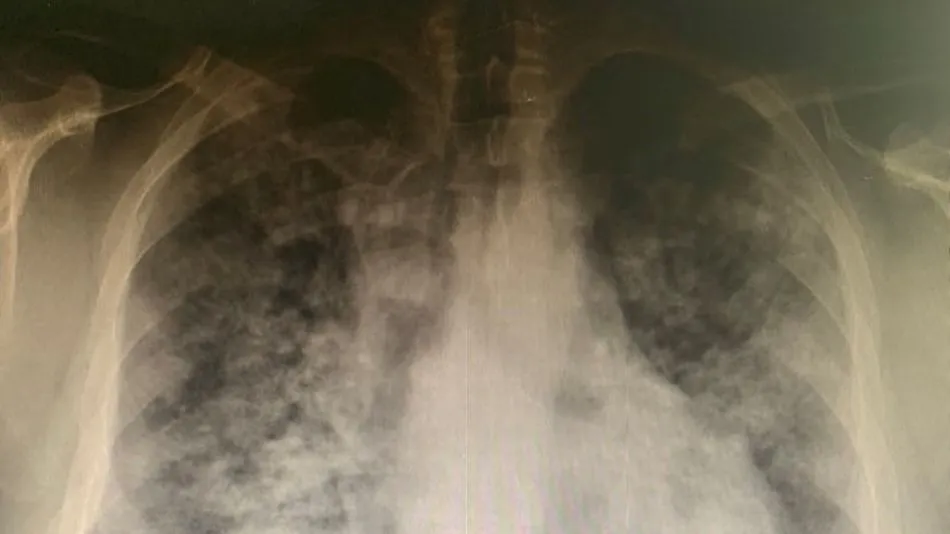

A pesar del tratamiento la fiebre no bajaba de 39. pic.twitter.com/SC6jYaFi1N